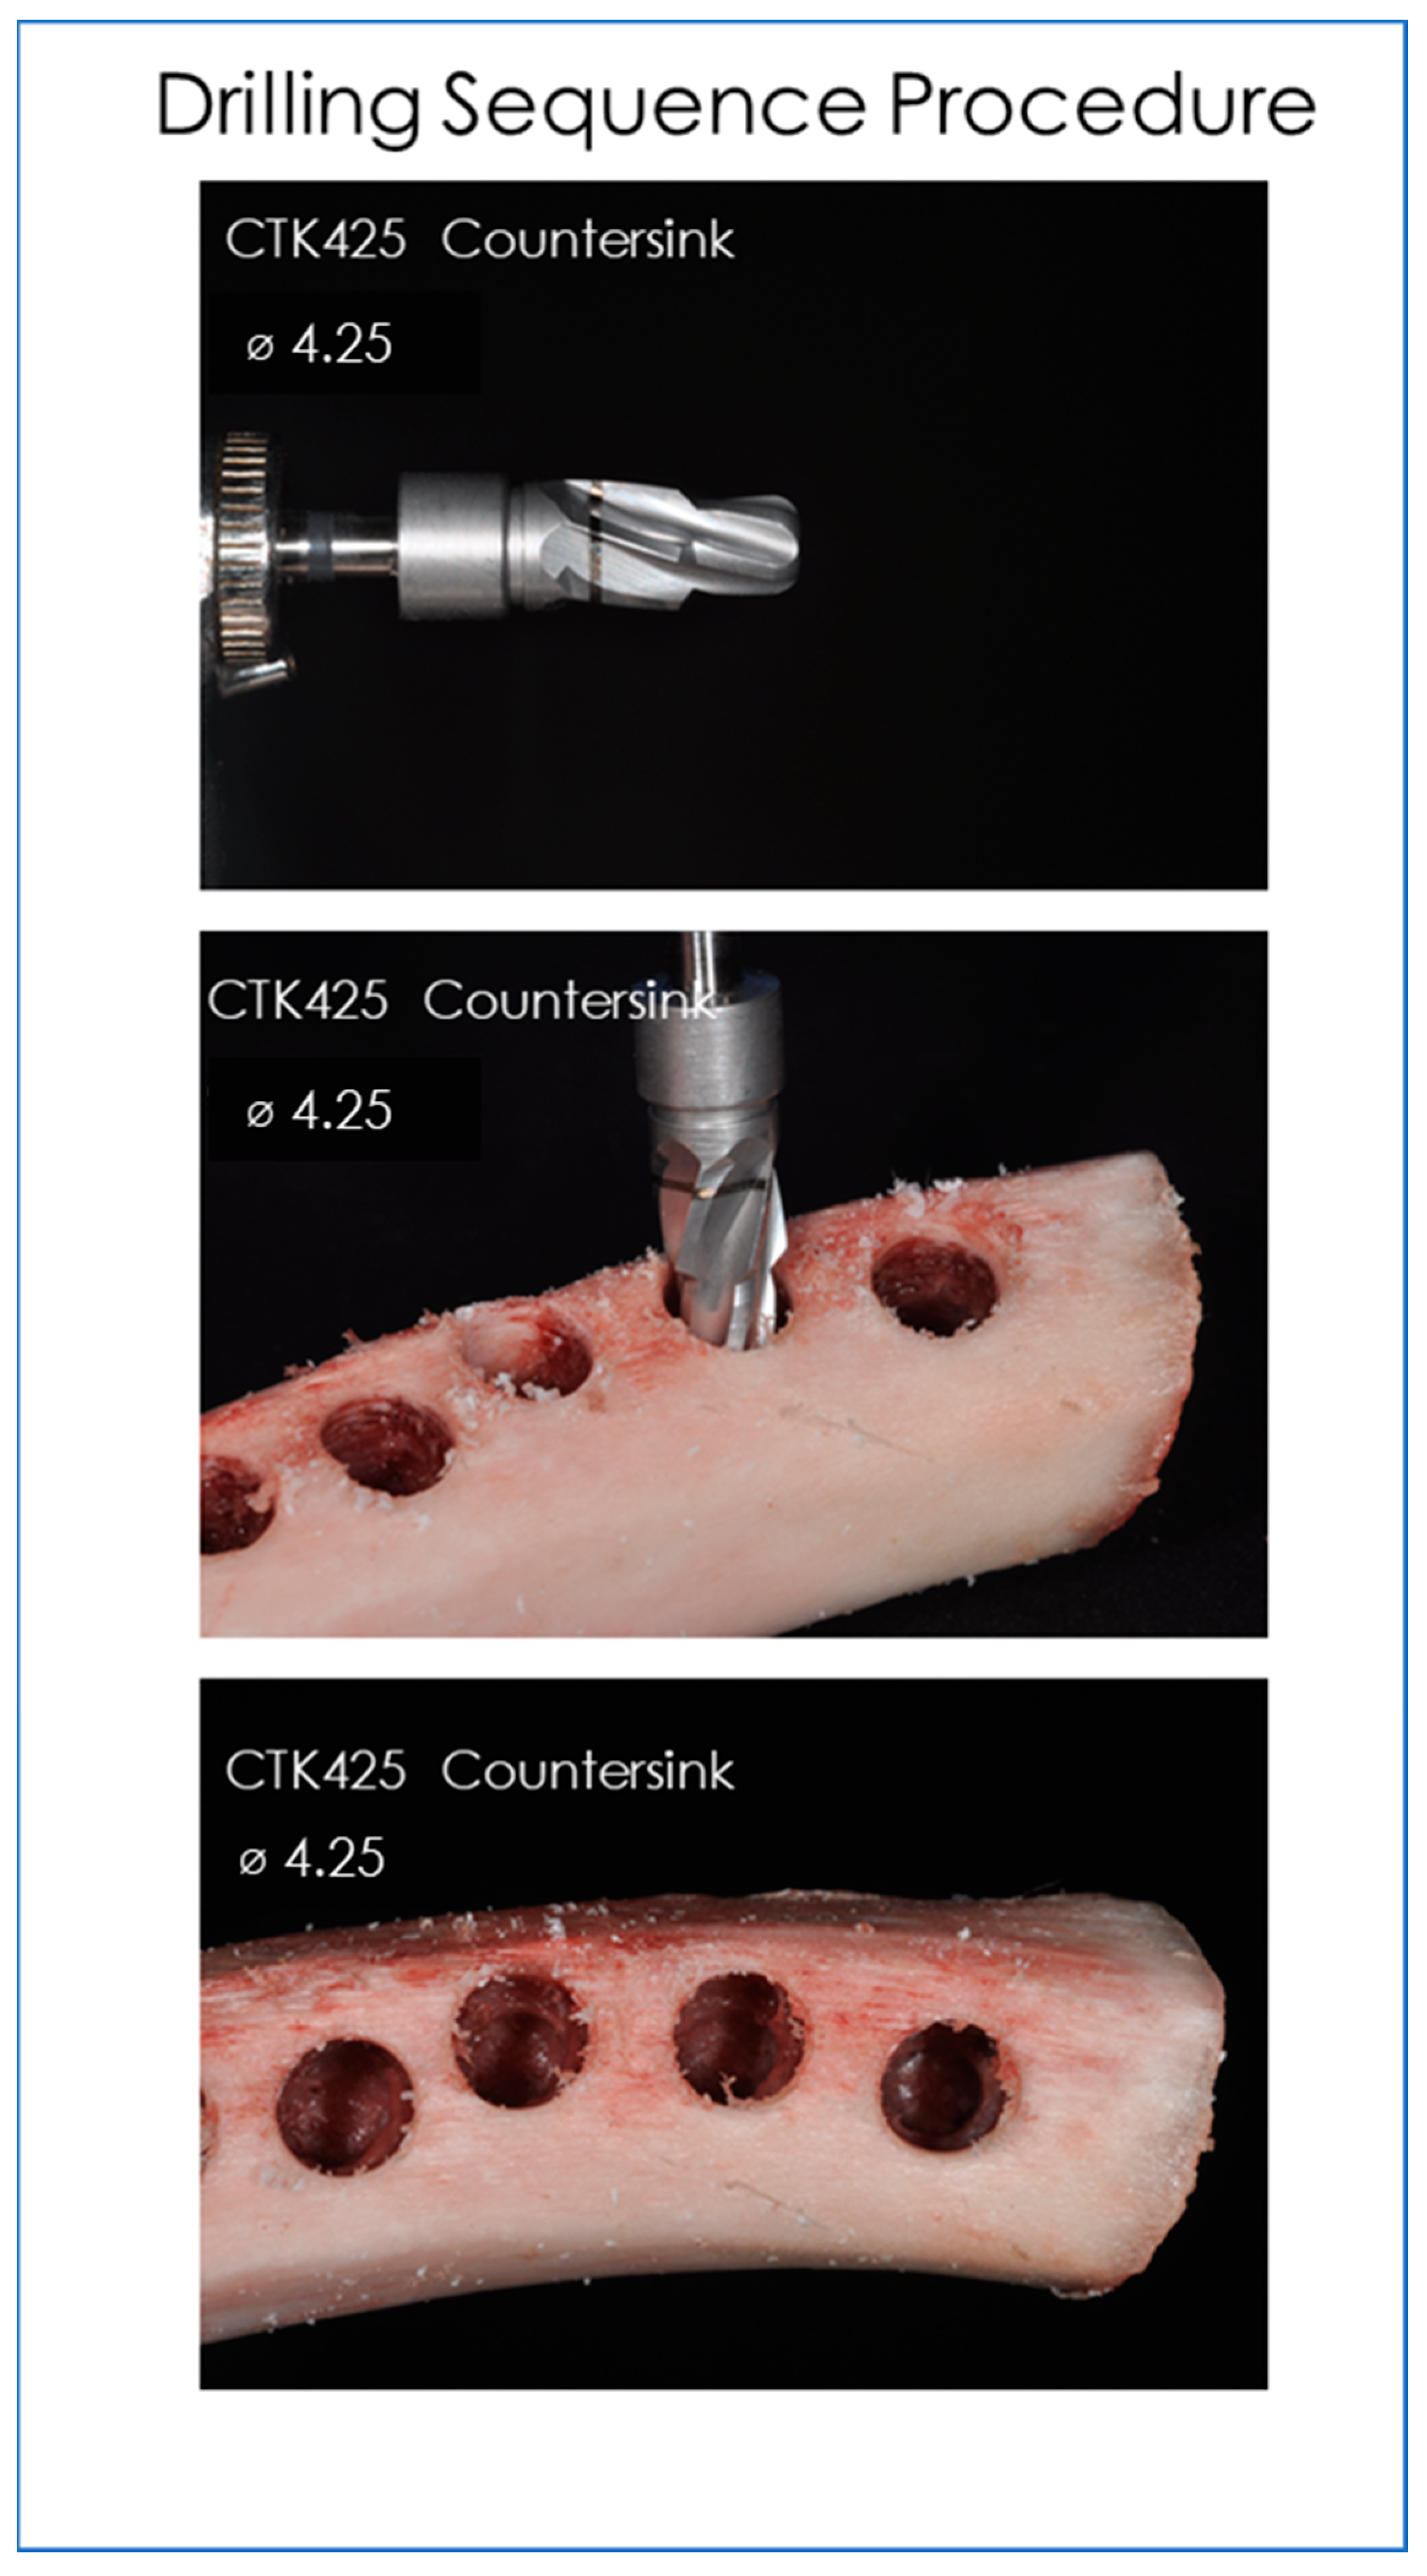

2. Materials and Methods

2.1. Drills and Bone Tappers Evaluated

2.2. Infrared Thermographic Measurements